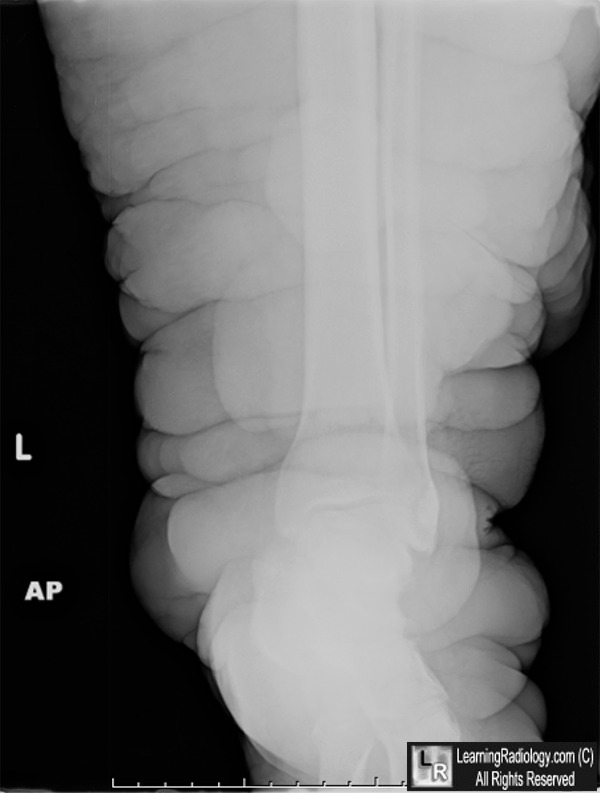

Lymphedema. There is marked soft tissue swelling of the left lower extremity. The patient had a negative workup for filarial disease and the leg was normal.